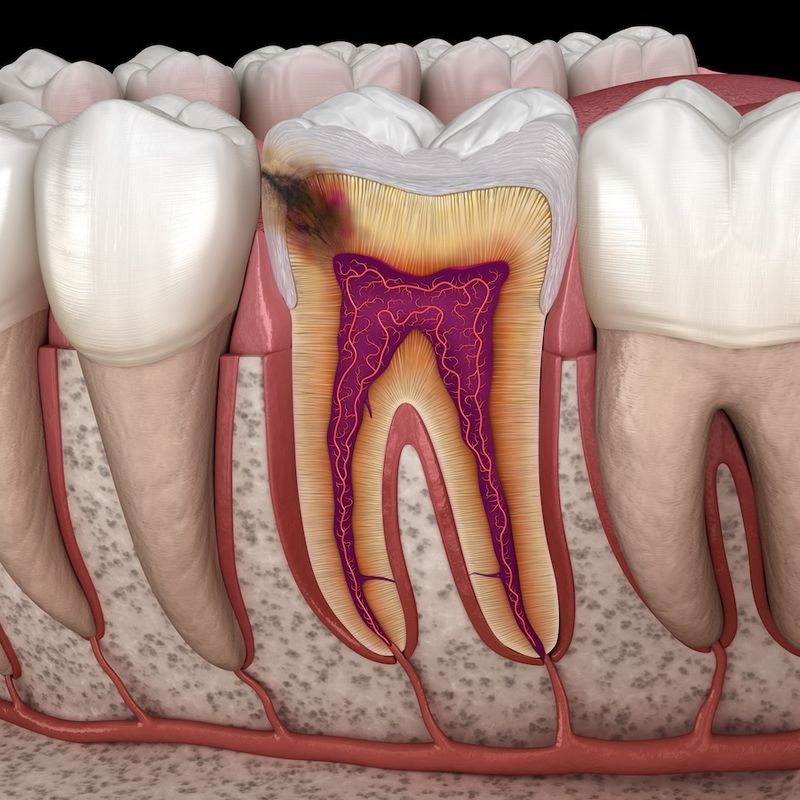

12. Bad Breath

Bad breath might emerge from an overconsumption of carbs, especially if your diet is high in simple sugars. These sugars can promote bacterial growth in the mouth, resulting in unpleasant breath. Combat this by maintaining good oral hygiene and reducing sugar intake.

Choosing whole foods and complex carbs can help improve your breath naturally, boosting your confidence during social interactions.

18. Swollen Gums

Swollen gums could signal too much sugar in your diet. Sugars nourish harmful bacteria in the mouth, causing gum inflammation.

Cutting back on sugar and focusing on whole foods helps protect oral health, reducing swelling and discomfort while encouraging a brighter, more confident smile.

27. Dental Cavities

Dental cavities often trace back to high sugar consumption. Sugars feed bacteria that produce acids, damaging teeth.

Cut back on sugar and maintain good oral hygiene. Proactive steps promote stronger teeth, reducing cavities and enhancing your smile.